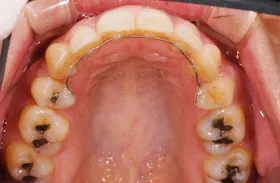

インプラント治療及び補綴治療のケース

■治療前:奥歯が無いため噛み合わせが深く下の歯が全く見えない

噛み合わせが低いため全体的に歯が削れている

■治療後:下顎 左下5・6番、右下4・6番にインプラント治療

その他の歯に補綴治療をしたことにより、奥歯もしっかりと咬むことができ、奥歯ができたことにより噛み合わせも上がって下の歯も見えるようになり、審美的にも改善された

| 主訴 | 歯科治療をしても歯がすぐに欠けてしまう 奥歯が無いため、奥歯で咬めない |

|---|---|

| 治療方法 | インプラント治療 + 補綴治療 |

| 治療期間 | 約1年 |

| 通院回数等 | 約20回 |

| 費用 | 約250万円(税込) |

| リスク・副作用 | 術後の腫れ・痛み |